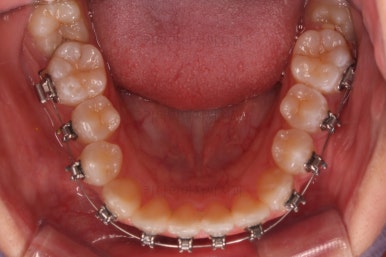

쓰러져 있던 치아도 장치를 부착하여 일으켜 세워주는 힘을 줍니다.

자칫 나머지 치열이 틀어질 수 있기 때문에 아랫니에는 미니스크류를 이용해서 반작용을 막아줍니다.

점점 뒤쪽 치아가 바로 일으켜 세워지고 있네요.